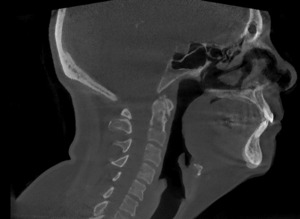

Pictured below is a neutral lateral radiograph (Figure 4) and sagittal slice of a CBCT image of the same patient (Figure 5)

It is important to keep in mind that chiropractors take multiple images of the same anatomic region when using traditional radiographs to obtain the necessary detail needed for proper treatment. As we begin to consider patient dose, the effective patient dose to obtain an image similar to that of Figure 4 (lateral cervical radiograph) is 0.02 mSv (20 μSv) and for an AP cervical spine radiograph is 0.12 mSv.7